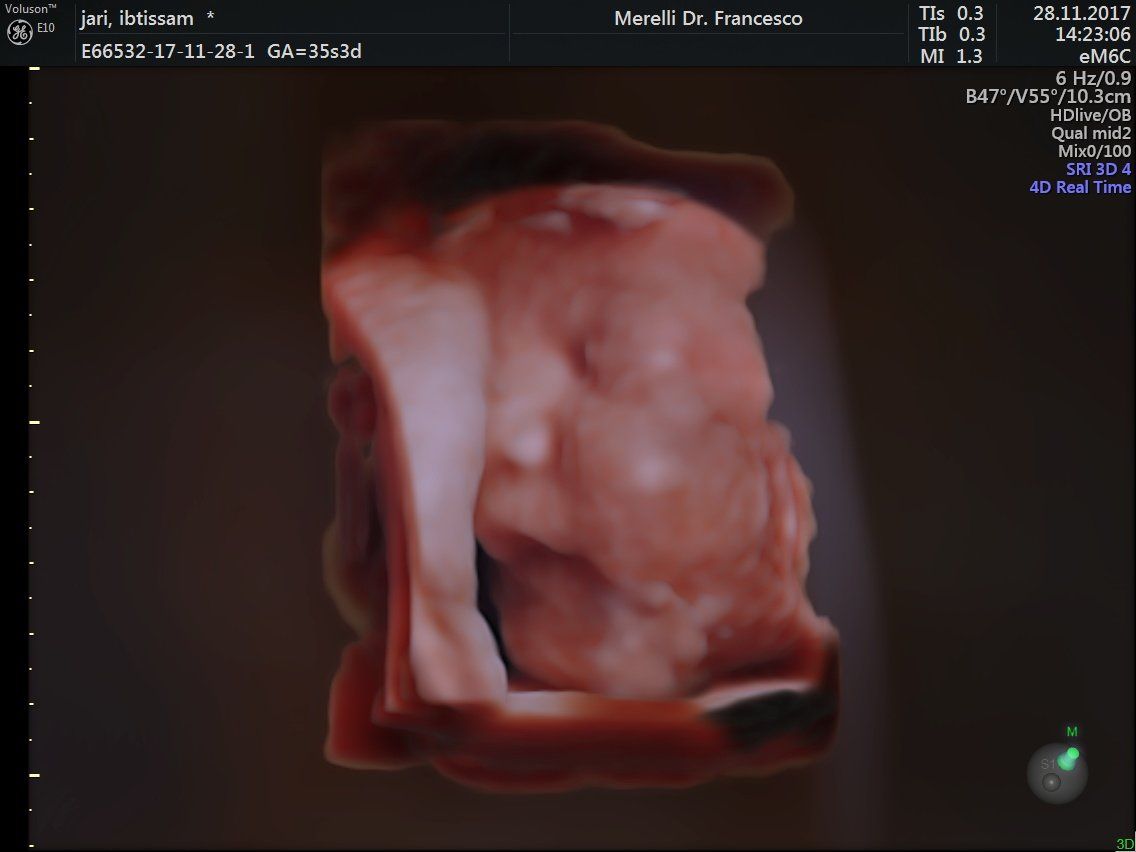

Il dr. Merelli esegue anche l'

ecografia ostetrica ginecologica tridimensionale.

- ecografie ostetrico - ginecologiche

- ecografia 4d